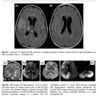

Labs: Initially, check glucose, chemistry profile —including calcium, magnesium, and phosphate —CBC, and urine toxicity screen ASM levels (if applicable). LP should be done if CNS infection, vasculitis, autoimmune, paraneoplastic, or meningeal neoplastic disease is suspected as a possible cause, after ruling out mass lesions with CT or MRI. Leukocytosis is commonly seen with SE without any infection because of blood–brain barrier breakdown during SE. CSF WBC counts of up to 30 x 10 ^6 can be seen. Continuous EEG monitoring should be started, if available, if SE has continued for >60 min. Neuroimaging changes associated with SE (Table 8.8; Figs. 8.1 and 8.2). MRI may be focally abnormal during both convulsive and non-convulsive status epilepticus. This may be misdiagnosed as acute lesions, e.g., stroke or encephalitis. Possible MRI abnormalities during SE include increased FLAIR (fluid-attenuated inversion recovery), T2 signal hyperintensity and high-intensity signal DWI (diffusion-weighted imaging), both local at seizure focus and remote, commonly in the ipsilateral posterior thalamus (pulvinar), contralateral cerebellum, and bilateral splenium of the corpus callosum (Table 8.8; Figs. 8.1 and 8.2). These changes may be due to the prolonged ictal activity increasing glucose utilization, which is not adequately matched by the enhanced blood flow. Blood flow–metabo- lism uncoupling leads to a reduction of high-energy adenosine phosphates and tissue hypoxia. The regional hyperperfusion serves as a compensatory mechanism, but is insufficient to prevent the stimulation of anaerobic glycolysis due to the prolonged ictal activity.

Peri-ictal MRI changes